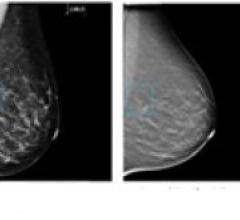

Despite decades of progress in breast imaging, one challenge continues to test even the most skilled radiologists ...

Hologic features its Selenia Dimensions, including Selenia Breast tomosynthesis that may alleviate the challenges created by overlapping breast tissue in a traditional mammogram by presenting a slice-by-slice view of the breast.